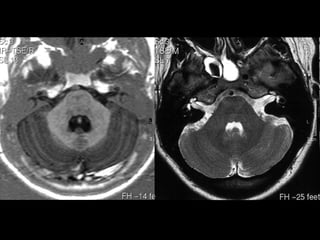

•   FORAME MAGNO

•   MEDULA ESPINHAL CERVICAL

•   ART. VERTEBRAIS

•   TONSILAS CEREBELARES

•   CLIVUS                • VALÉCULA. FORAME DE

•   CANAL DO HIPOGLOSSO     MAGENDIE

• CISTERNAS

•   BULBO

• MAGNA

•   AMÍGDALAS

• PRÉ BULBAR

•   ART. VERTEBRAIS             • CEREBELO-BULBAR

•   BULBO JUGULAR         • PROTUBERÂNCIA OCCIPTAL

• PIRÂMIDES

• OLIVAS

• SULCOS

– PRÉ OLIVAR

– PÓS OLIVAR

•   AMÍGDALAS CEREBELARES / LOBO BIVENTRAL (+LAT)

•   FORAMES DE LUSCHKA

•   PICA

•   SEIOS SIGMÓIDES

• PONTE

• PEDÚNCULO CEREBELARES MÉDIOS / CORPOS

MEDULARES        NÓDULO

VERMIS   ÚVULA

PIRÂMIDE

• CEREBELO                 FLÓCULO

HEMISFÉRIOS

SEMILUNAR

• ARTÉRIA BASILAR

• IV VENT.

• CISTERNAS PRÉ-PONTINA

CEREBELO-PONTINA

• CONDUTOS AUDITIVOS

INTERNOS

• PONTE - COLÍCULOS FACIAIS

• PEDÚNCULOS CEREBELARES MÉDIOS / CORPOS MEDULARES

• CEREBELO

VÉRMIS - NÓDULO, ÚVULA, PIRÂMIDE

• CISTERNA      HEMISFÉRIOS

PRÉ-PONTINA

• C.A.I.       CEREBELO-PONTINA